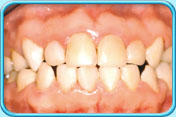

由於恆齒的琺瑯質是稍微透明的,內層黃色的象牙質就透現出來,所以恆齒會呈微黃色。隨年紀漸長,象牙質不斷增厚,牙齒亦會變得比較黃,這情況是正常的。

呈微黃色的恆齒乳齒的琺瑯質不及恆齒的琺瑯質那般透明,因此乳齒呈乳白色。